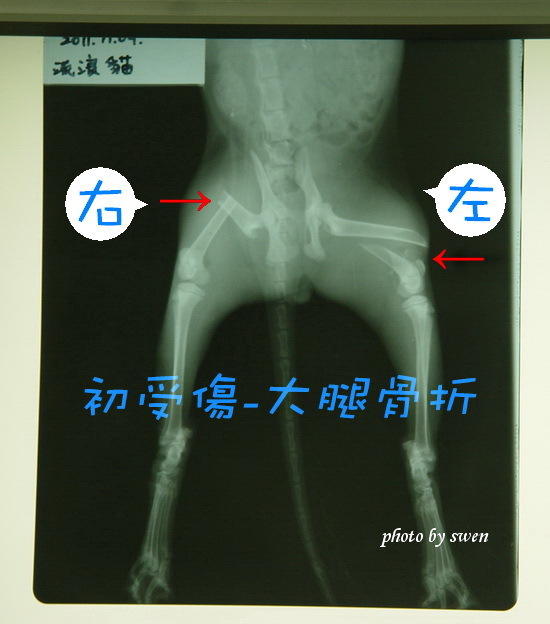

主題: 呼嚕雙腿骨折二次重建 申請者姓名: 詹淑雲 花色: 申請日期: 2012-04-01 15:14:35 申請者部落格: http://blog.sina.com.tw/swen/article.php?pbgid=60531&entryid=638843 申請者臉書網址: 所在縣市/合作醫院: 新北市/成蹊動物醫院 治療費用: 27000元 需求人數: 27人 已結案 (2012-05-14 16:29:32) 報名人員: Serious Jerry(已付款)、Calla Shen(已付款)、harushi(已付款)、TH Taiwan Forum(已付款)、陳宗榮(已付款)、Annie Huang(已付款)、Susan SY Lin、pin pn(已付款)、Ping Hussard(已付款)、陳明蘭(已付款)、kelly(已付款)、Vickie M. Hsu(已付款)、劉蕊瑄(已付款)、Elaine、sandy_huanglichuan(已付款)、Ling Chou(已付款)、Yen-Yuan Wang(已付款)、江大雄(已付款)、雲逍遙(已付款)、Angus Young、Vickie M. Hsu(已付款)、Choco Cheng(已付款)、爪爪(已付款)、張角倫(已付款)、cheselingna(已付款)、Gina Pien、H.l. Lai(已付款)、Phoebe Lee(已付款)、Mimi(已付款)、Cecilia Lee(已付款)、Mavis Yu(已付款)、 候補人員: 動物病情說明: 100年11月被一般民眾撿到醫院丟包的小貓

兩隻大腿骨折嚴重骨折,由醫院手術開刀接合治療

1.左腳斷骨有癒合但腳掌已經萎縮,日前也將原醫院術後移位的骨釘拆除

2.右腳斷骨沒有接合,所以必須重新開刀再接一次,而這次必須使用骨板接合